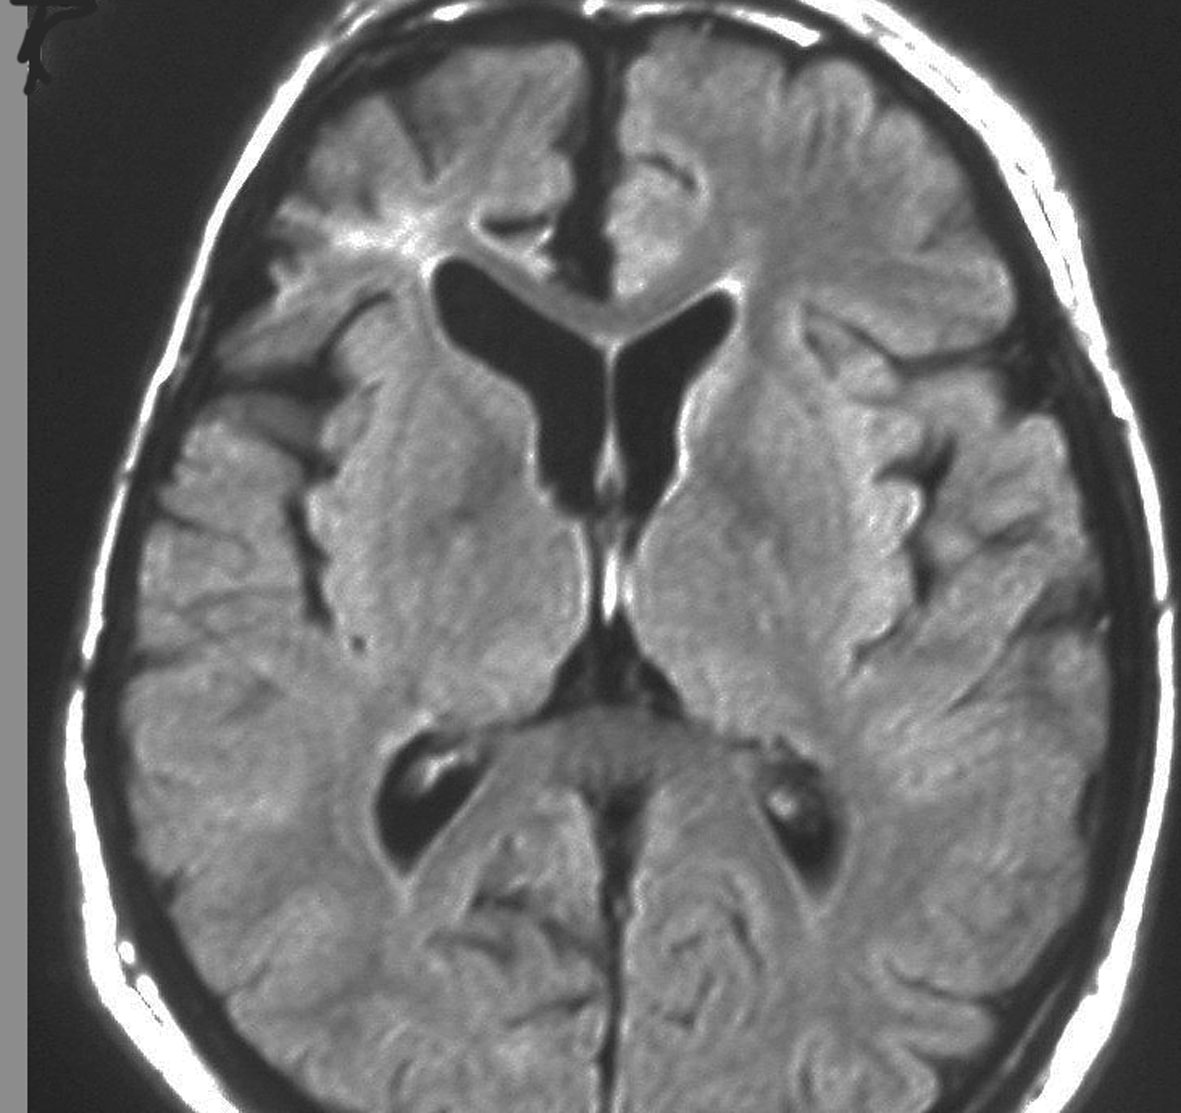

クラニオと視床下部,視索の浮腫

成人ののう胞性頭蓋咽頭腫 cystic craniopharyngioma です。腫瘍の周囲の視床下部に浮腫があります。右視索から内包への浮腫も顕著でした。このために認知機能障害で発症しました。この視床下部性の認知機能障害は可逆的で,手術で視床下部損傷をしないように腫瘍摘出すると認知機能は正常に戻ります。